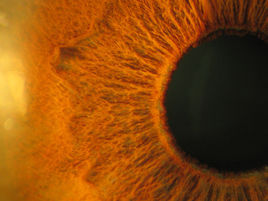

人眼的虹膜,周邊黃褐色的為虹膜,中間黑色為瞳孔虹膜識別的發展歷程可以追溯至19世紀80年代。

虹膜虹膜是眼睛構造的一部分,虹膜中心有一圓形開口,稱為瞳孔,猶如相機當中可調整大小的光圈,內含色素決定眼睛的顏色。日間光線較為強烈時,虹膜會收蹜,只使一小束光線穿透瞳孔,進入眼睛;當進入黑暗環境中,虹膜就會往後退縮,使瞳孔變大,讓更多的光線進入眼睛,多數的脊椎動物的眼睛都有虹膜。